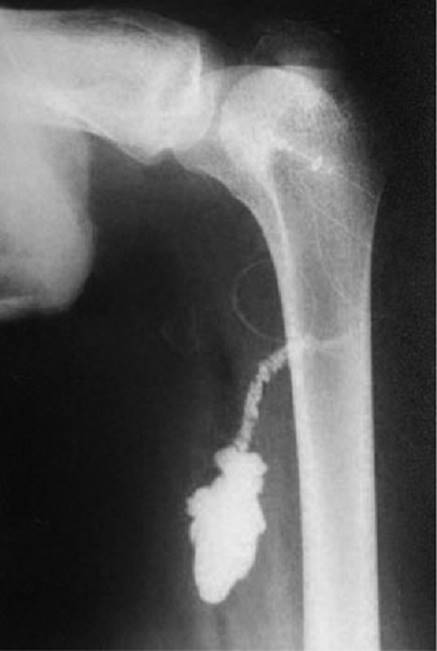

6. In the recovery room, a radiograph may be performed after injection of a contrast agent to verify the position of the parasacral catheter.